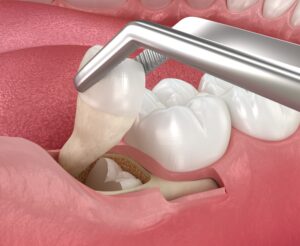

아래턱 왼쪽 사랑니(#38)의 경우

아래턱 하방으로 지나가는

하치조 신경과 사랑니 뿌리 끝이

근접해 있었는데요.

발치 시 신경을 건드리게 되면

감각 이상 등

부작용이 일어날 수 있기 때문에

양산수면치과 중부에이디치과에서는

파노라마 사진과 3D CT 촬영을 통해

사랑니의 위치와 방향,

하치조 신경관의 위치 등

육안으로 판단이 어려운

해부학적인 구조물까지 면밀하게 파악 후

대표 원장님께서 다양한 임상경험을 바탕으로

편안하고 안정적으로

왼쪽 위 위아래 사랑니 발치를

도와드렸습니다.